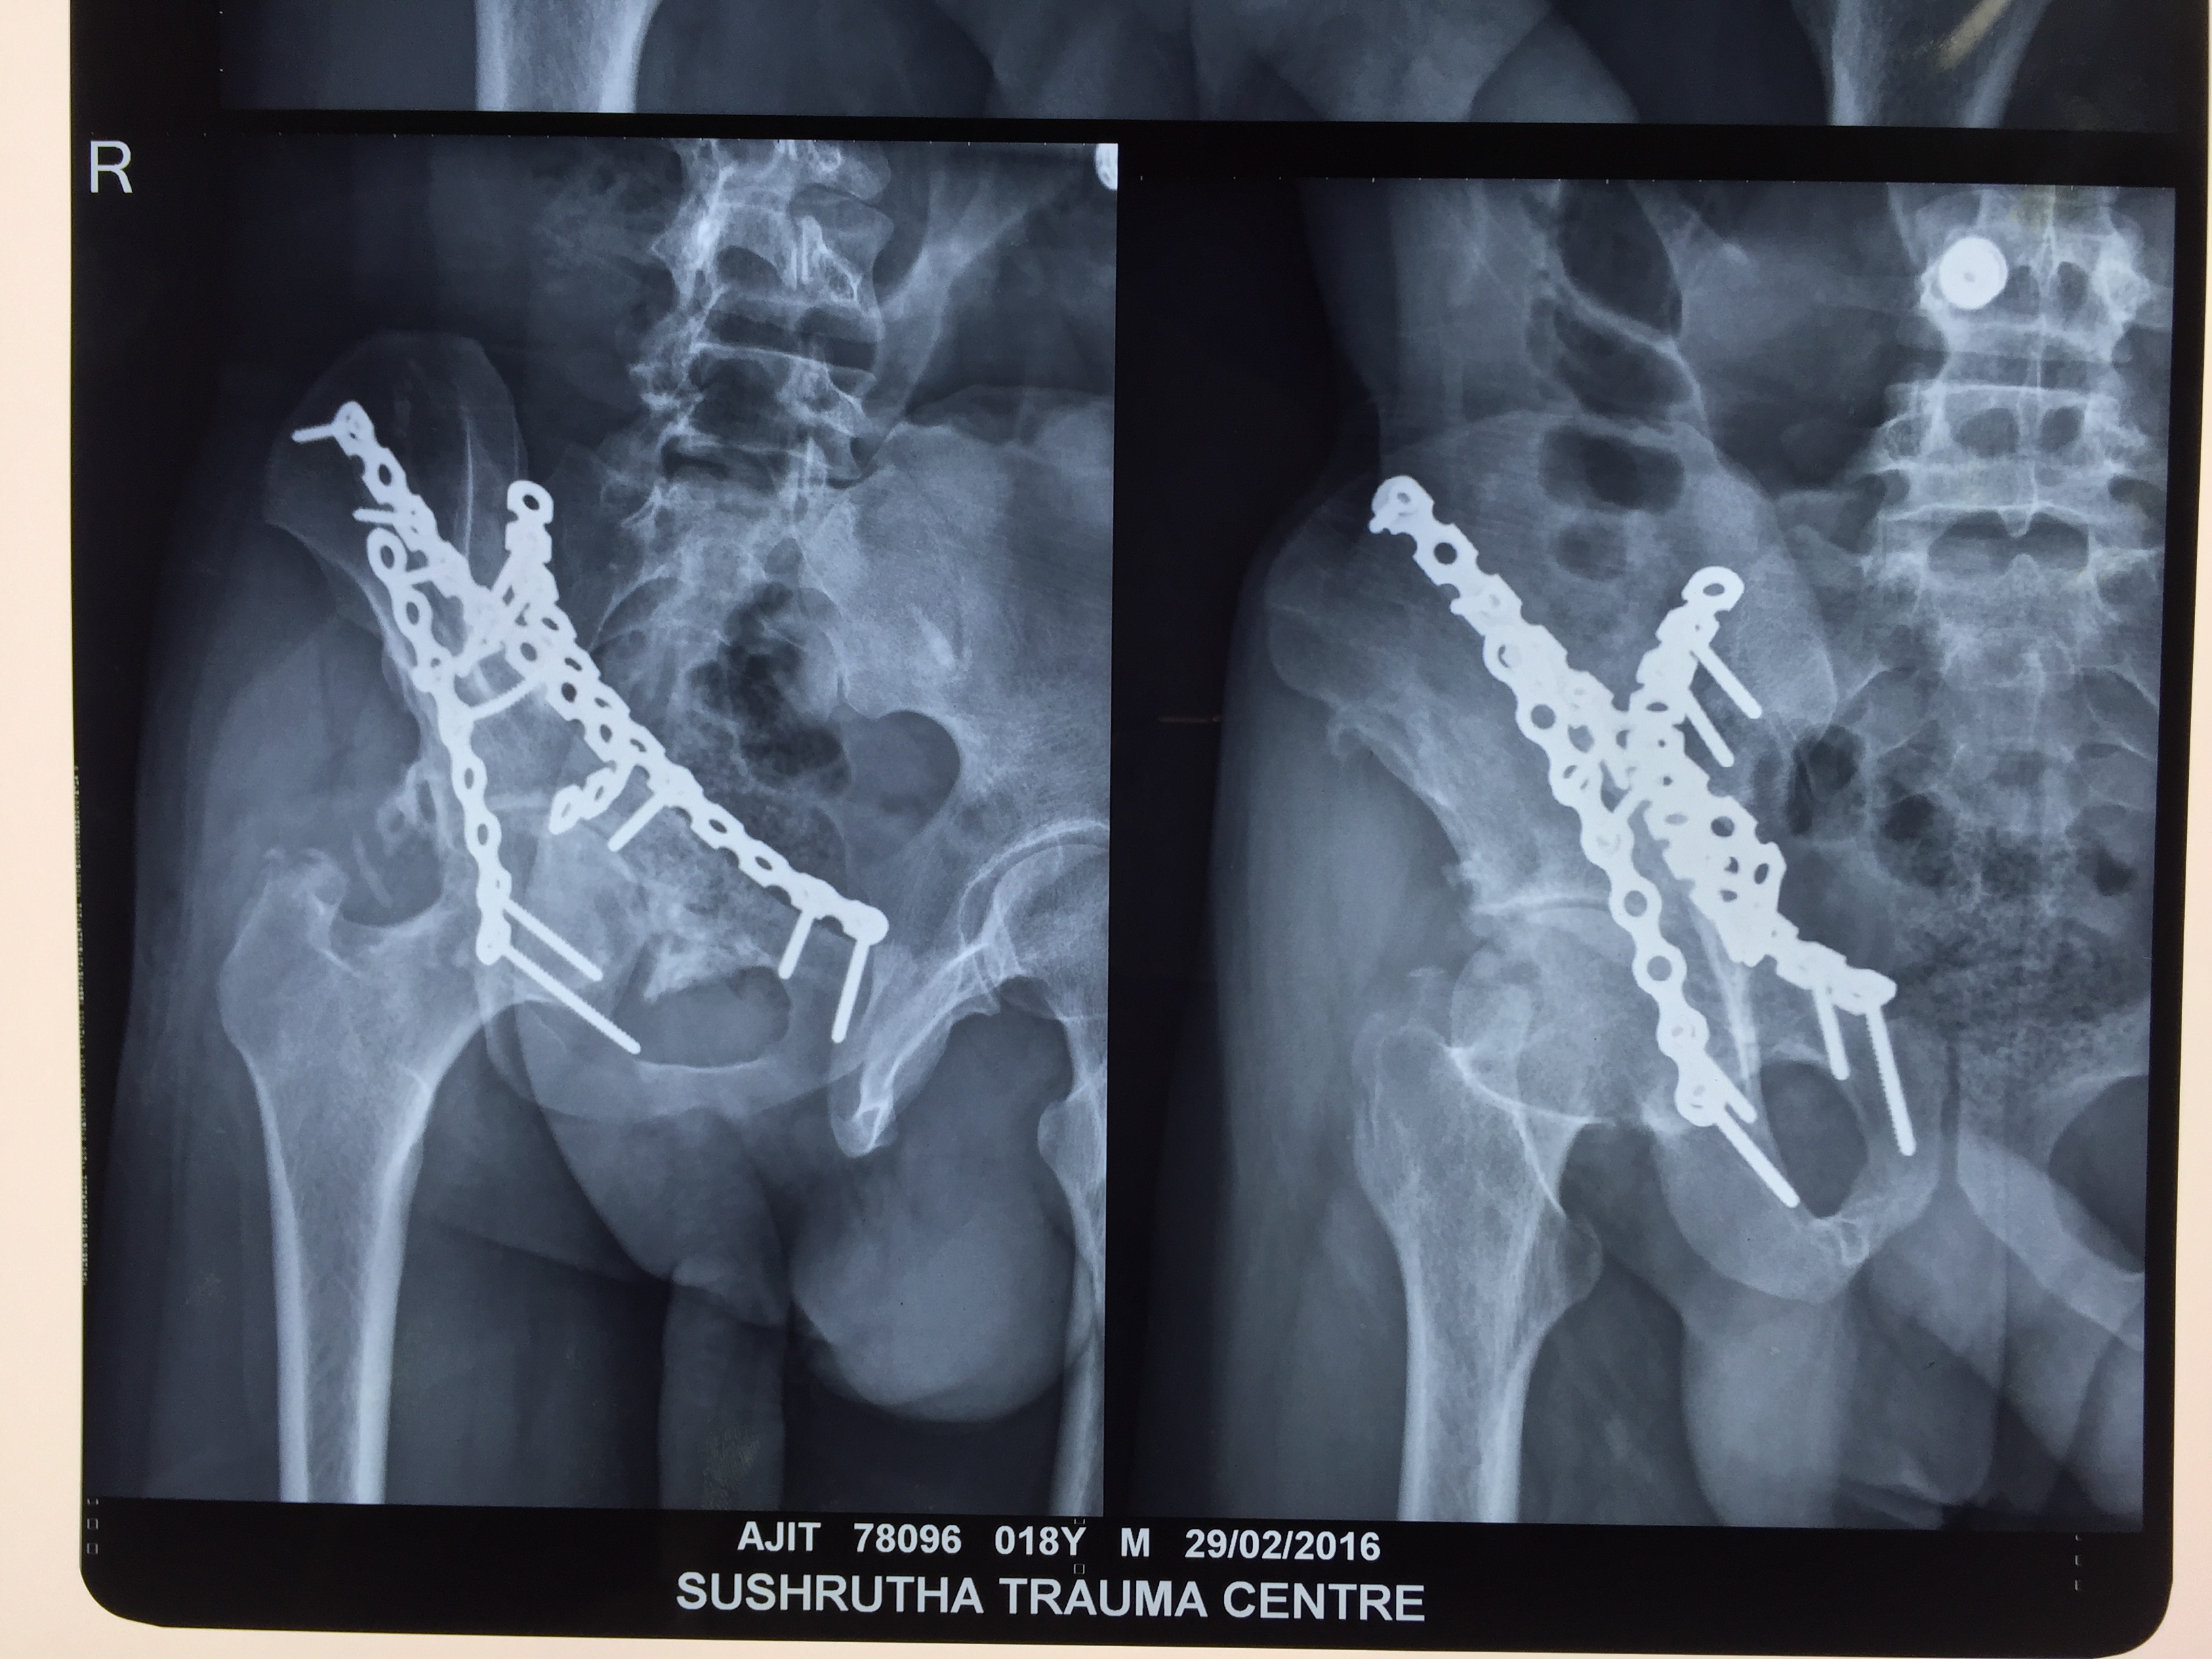

A doctor will reduce the fracture for the natural healing process to begin. This involves lining up the ends of the broken bones. A doctor can do this in more minor fractures by manipulating the affected area externally. However, in some instances, this may require surgery.

Once a medical professional has aligned the fracture, they will ensure it stays in place. Methods of doing so are –

- casts or braces

- metal plates and screws

- intramedullary nails, or rods, placed in bone cavities

- external fixings